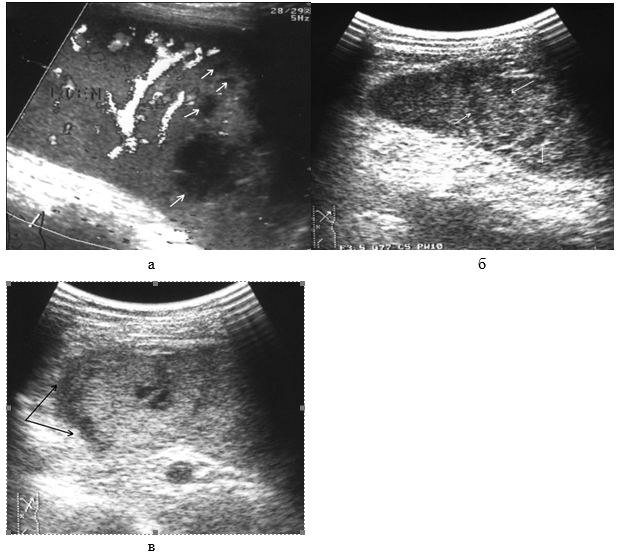

Прямым и наиболее постоянным (в течение острого периода травмы) эхографическим признаком подкапсульных разрывов селезенки с образованием внутриорганных гематом является наличие в паренхиме эхонегативной зоны (рис. 2, а, б). При гематомах, локализовавшихся в области полюсов селезенки или по ее диафрагмальной поверхности, эхонегативная зона имеет серповидную форму, повторявшую контур органа (рис. 2, в).

Рис. 2. Эхограмма подкапсульного разрыва селезенки: а – внутриорганная гематома; б – линейные разрывы паренхимы; в – подкапсульная гематома.

Необходимо указать, что при первичном исследовании (3–5 часов после травмы) ни в одном наблюдении не представилось возможности достоверно выявить подкапсульный разрыв селезенки в виде эхонегативной зоны. Повреждения визуализировались как нечетко очерченные участки паренхимы с незначительно сниженной эхогенностью, имевшие «смазанную» структуру, нехарактерную для паренхимы селезенки (рис 3).

Рис. 3. Эхограмма подкапсульного разрыва селезенки (3–5 часов после травмы). Зона повреждения указана стрелками.

Сканирование селезенки через 8–12 часов после травмы позволяет выявить прогрессирующее неравномерное снижение акустической плотности в зоне интереса (рис. 4, а). Устойчивая визуализация эхонегативной зоны (внутритканевой гематомы) становится возможной по истечении первых суток посттравматического периода (рис. 4, б).

Рис. 4. Эхограмма подкапсульного разрыва селезенки: а – через 8–12 часов после травмы; б – через 1 сутки после травмы.

В ряде случаев выявляется несколько эхонегативных зон, расположенных в непосредственной близости. Практически в половине наблюдений в травматической полости визуализируются эхопозитивные фрагменты различных размеров и формы, представляющим собой сгустки крови и тканевые секвестры (рис. 5, а, б). Подобная точка зрения подтверждается их обратным развитием с образованием мелкодисперсной взвеси осадка в содержимом полости по истечении 7–10-ти суток после травмы.

Эхографически эволюция внутриорганных гематом характеризуется прогрессивным сокращением объема травматической полости, снижением четкости контуров, неоднородным повышением эхогенности ее содержимого за счет заполнения множественными точечными структурами, соответствующими по эхогенности паренхиме селезенки (рис. 6).

Рис. 5. Эхограмма подкапсульного разрыва селезенки: а – сгусток крови в посттравматической полости; б – тканевый секвестр в посттравматической полости.

Рис. 6. Репаративная регенерация при травме селезенки. Точечные эхосигналы в посттравматической полости указаны стрелками.